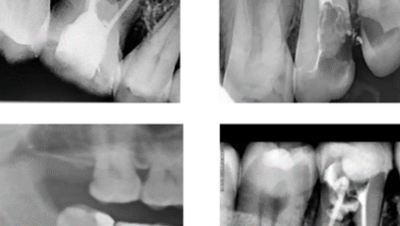

Het Belang van Röntgenfoto's in Endodontie: Essentiële Inzichten voor Tandheelkundige Zorg